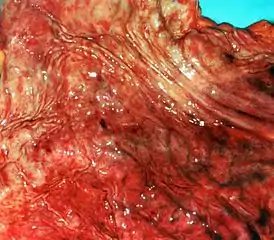

Гастри́т (лат. gastritis, от др.-греч. γαστήρ [gaster] «желудок» + суффикс -itis «воспаление») — воспалительные или воспалительно-дистрофические изменения слизистой оболочки желудка; длительно протекающее заболевание, характеризуется дистрофически-воспалительными изменениями, протекает с нарушением регенерации, а также с атрофией эпителиальных клеток и замещением нормальных желёз на фиброзную ткань.

Коррозийный гастрит (лат. gastritis corrosiva, син. некротический гастрит, токсико-химический гастрит) возникает из-за попадания в желудок концентрированных кислот или щёлочей, солей тяжёлых металлов. Коррозийный гастрит характеризуется некротическими изменениями тканей желудка.